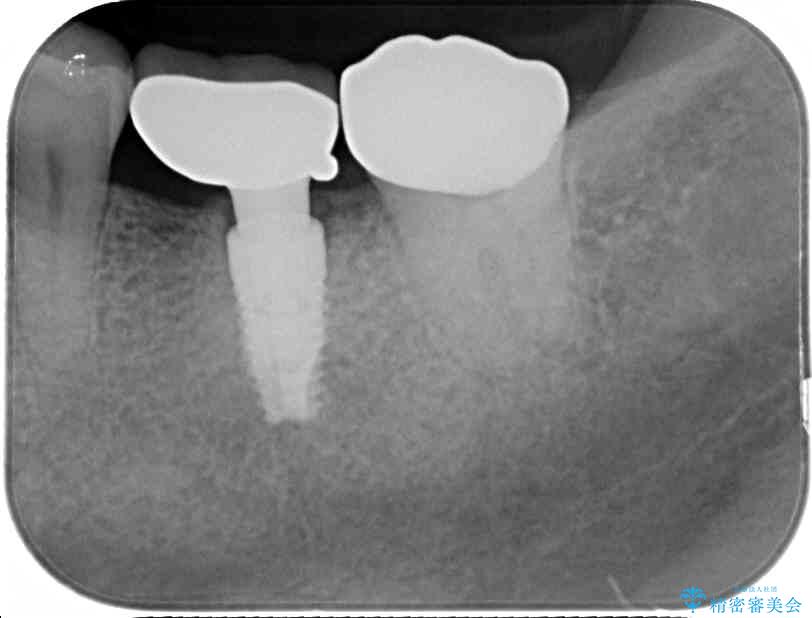

治療前

• しみる奥歯 オールセラミッククラウンによる補綴治療 治療前画像

銀歯周辺の歯が欠けており、むし歯も進行している状態であったので、オールセラミッククラウンにて補綴治療を行うこととしました。

治療途中